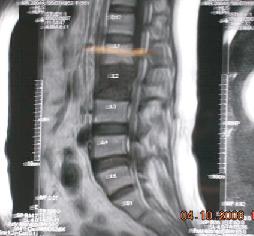

Lumbar Spinal Metastasis

Spine Tumor Surgery

A spinal tumor is an abnormal mass of tissue within or surrounding the spinal cord and/or spinal column. These cells grow and multiply uncontrollably, seemingly unchecked by the mechanisms that control normal cells.